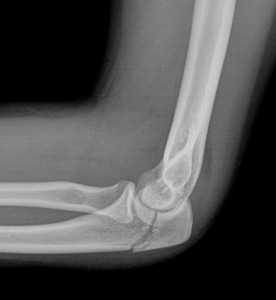

(Справа) На боковой рентгенограмме у ребенка после падения определяется косой перелом через среднюю точку локтевого отростка с незначительным смещением. Напротив, зона роста локтевого отростка волнистая с выраженным кортикальным слоем по краям. (Слева) На боковой рентгенограмме локтевого сустава после падения на вытянутую руку при согнутом локтевом суставе виден смещенный отломок, оторвавшийся от кончика локтевого отростка. Степень смещения свидетельствует о значительном повреждении трехглавой мышцы.

(Справа) На сагиттальной МРТ PDBИ определяется частичный отрыв сухожилия трехглавой мышцы с небольшим оторвавшимся костным отломком МРТ может быть информативна при оценке степени повреждения трехглавой мышцы. (Слева) На сагиттальной КТ с реформатированием можно видеть раздробление локтевого отростка после падения на локтевой сустав. Перелом открывается на суставную поверхность в нескольких местах.